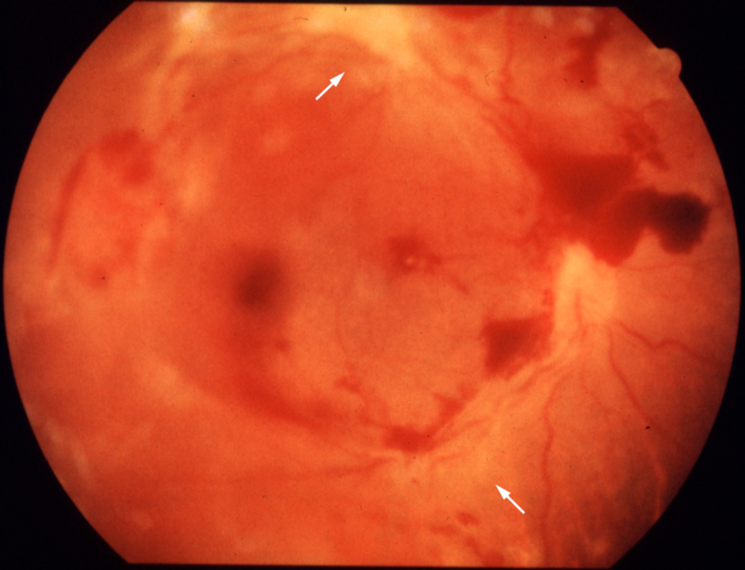

網脈絡膜炎

眼底検査でトキソプラズマ性網脈絡膜炎の特徴と考えられた網膜病変の形態。通常、活発な白色浸潤病巣は古い瘢痕の濃く色素沈着した縁部に隣接する。